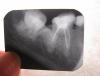

Krio Опубликовано 5 октября, 2012 Поделиться Опубликовано 5 октября, 2012 Уважаемые стоматологи!Буду очень признательна, если Вас не затруднит глянуть снимок. к вечеру возникли симптомы, а лечащий врач будет только в понедельник. а снимок сделать успела.это нижняя восьмерка, вдруг сегодня ее почувствовала как "выросший зуб" при накусывании, боли нет, но некий дискомфорт. ее пломбировали около года-двух назад, не депульпировали. семерки нет. почитала про признаки периодонтита, стало не по себе... может быть, что-то можно сказать по снимку? очно к врачу, конечно же, пойду.заранее большое спасибо.Анна. Ссылка на комментарий

DokDent Опубликовано 6 октября, 2012 Поделиться Опубликовано 6 октября, 2012 Уважаемые стоматологи!Буду очень признательна, если Вас не затруднит глянуть снимок. к вечеру возникли симптомы, а лечащий врач будет только в понедельник. а снимок сделать успела.это нижняя восьмерка, вдруг сегодня ее почувствовала как "выросший зуб" при накусывании, боли нет, но некий дискомфорт. ее пломбировали около года-двух назад, не депульпировали. семерки нет. почитала про признаки периодонтита, стало не по себе... может быть, что-то можно сказать по снимку? очно к врачу, конечно же, пойду.заранее большое спасибо.Анна. Анна,периодонтит возможен.Есть ли смысл сохранять этот зуб-обсудите с ортопедом.+ к Ивану-5 и 6 зубы перелечить и протезировать. Ссылка на комментарий